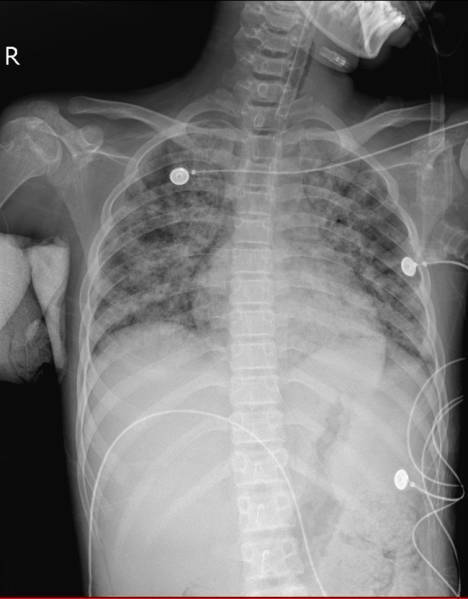

确定治疗方向后,由于病情急剧进展,患儿于入院第三天转入ICU治疗。在呼吸机给予100%纯氧的情况下,患儿病情依然危重,床旁胸片显示患儿肺部感染十分严重。联合院内体外循环,儿科,胸外,心外科多科室专家,ICU刘主任与各位专家认为患儿具备ECMO指征。运用经皮穿刺技术为患儿应用“人工肺”,机器运转后,患儿的血氧饱和度迅速上升至97%,效果显著。

检索万方和知网,目前国内无耶氏肺孢子虫肺炎接受ECMO治疗的报道。重症医学科治疗及护理团队面临严峻挑战。患儿患病期间ICU团队与体外循环团队紧密合作,针对患儿的病情变化不间断的调整治疗方案,患儿在运用“人工肺”9天之后成功下机,肺部感染情况有了非常大的改善。15天后脱离危险,转回普通病房继续治疗,目前没有气促,不需氧疗,体温正常,生活能够自理,之后痊愈出院。

患儿治疗后胸片